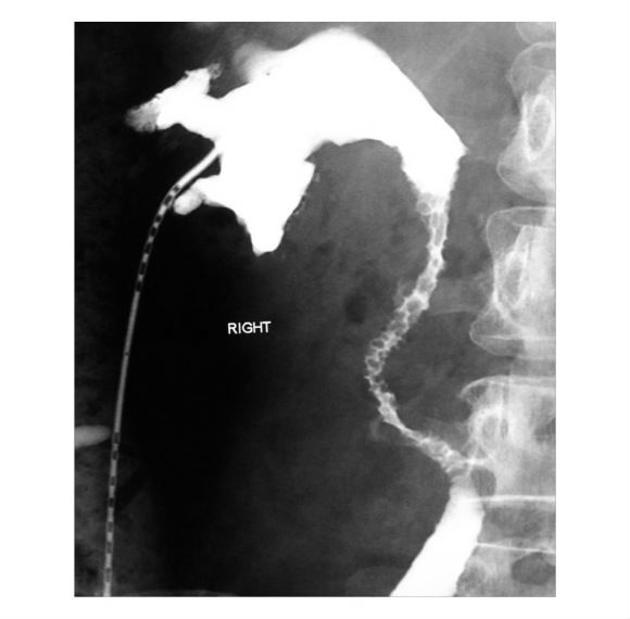

focal urethritis cystica

multiple small 2-5 mm smooth-walled rounded lucent filling defects projecting into the lumen

condition is seen in diabetics with recurrent urinary tract infections. As such, it is most frequently seen in older patients and is more common in women.